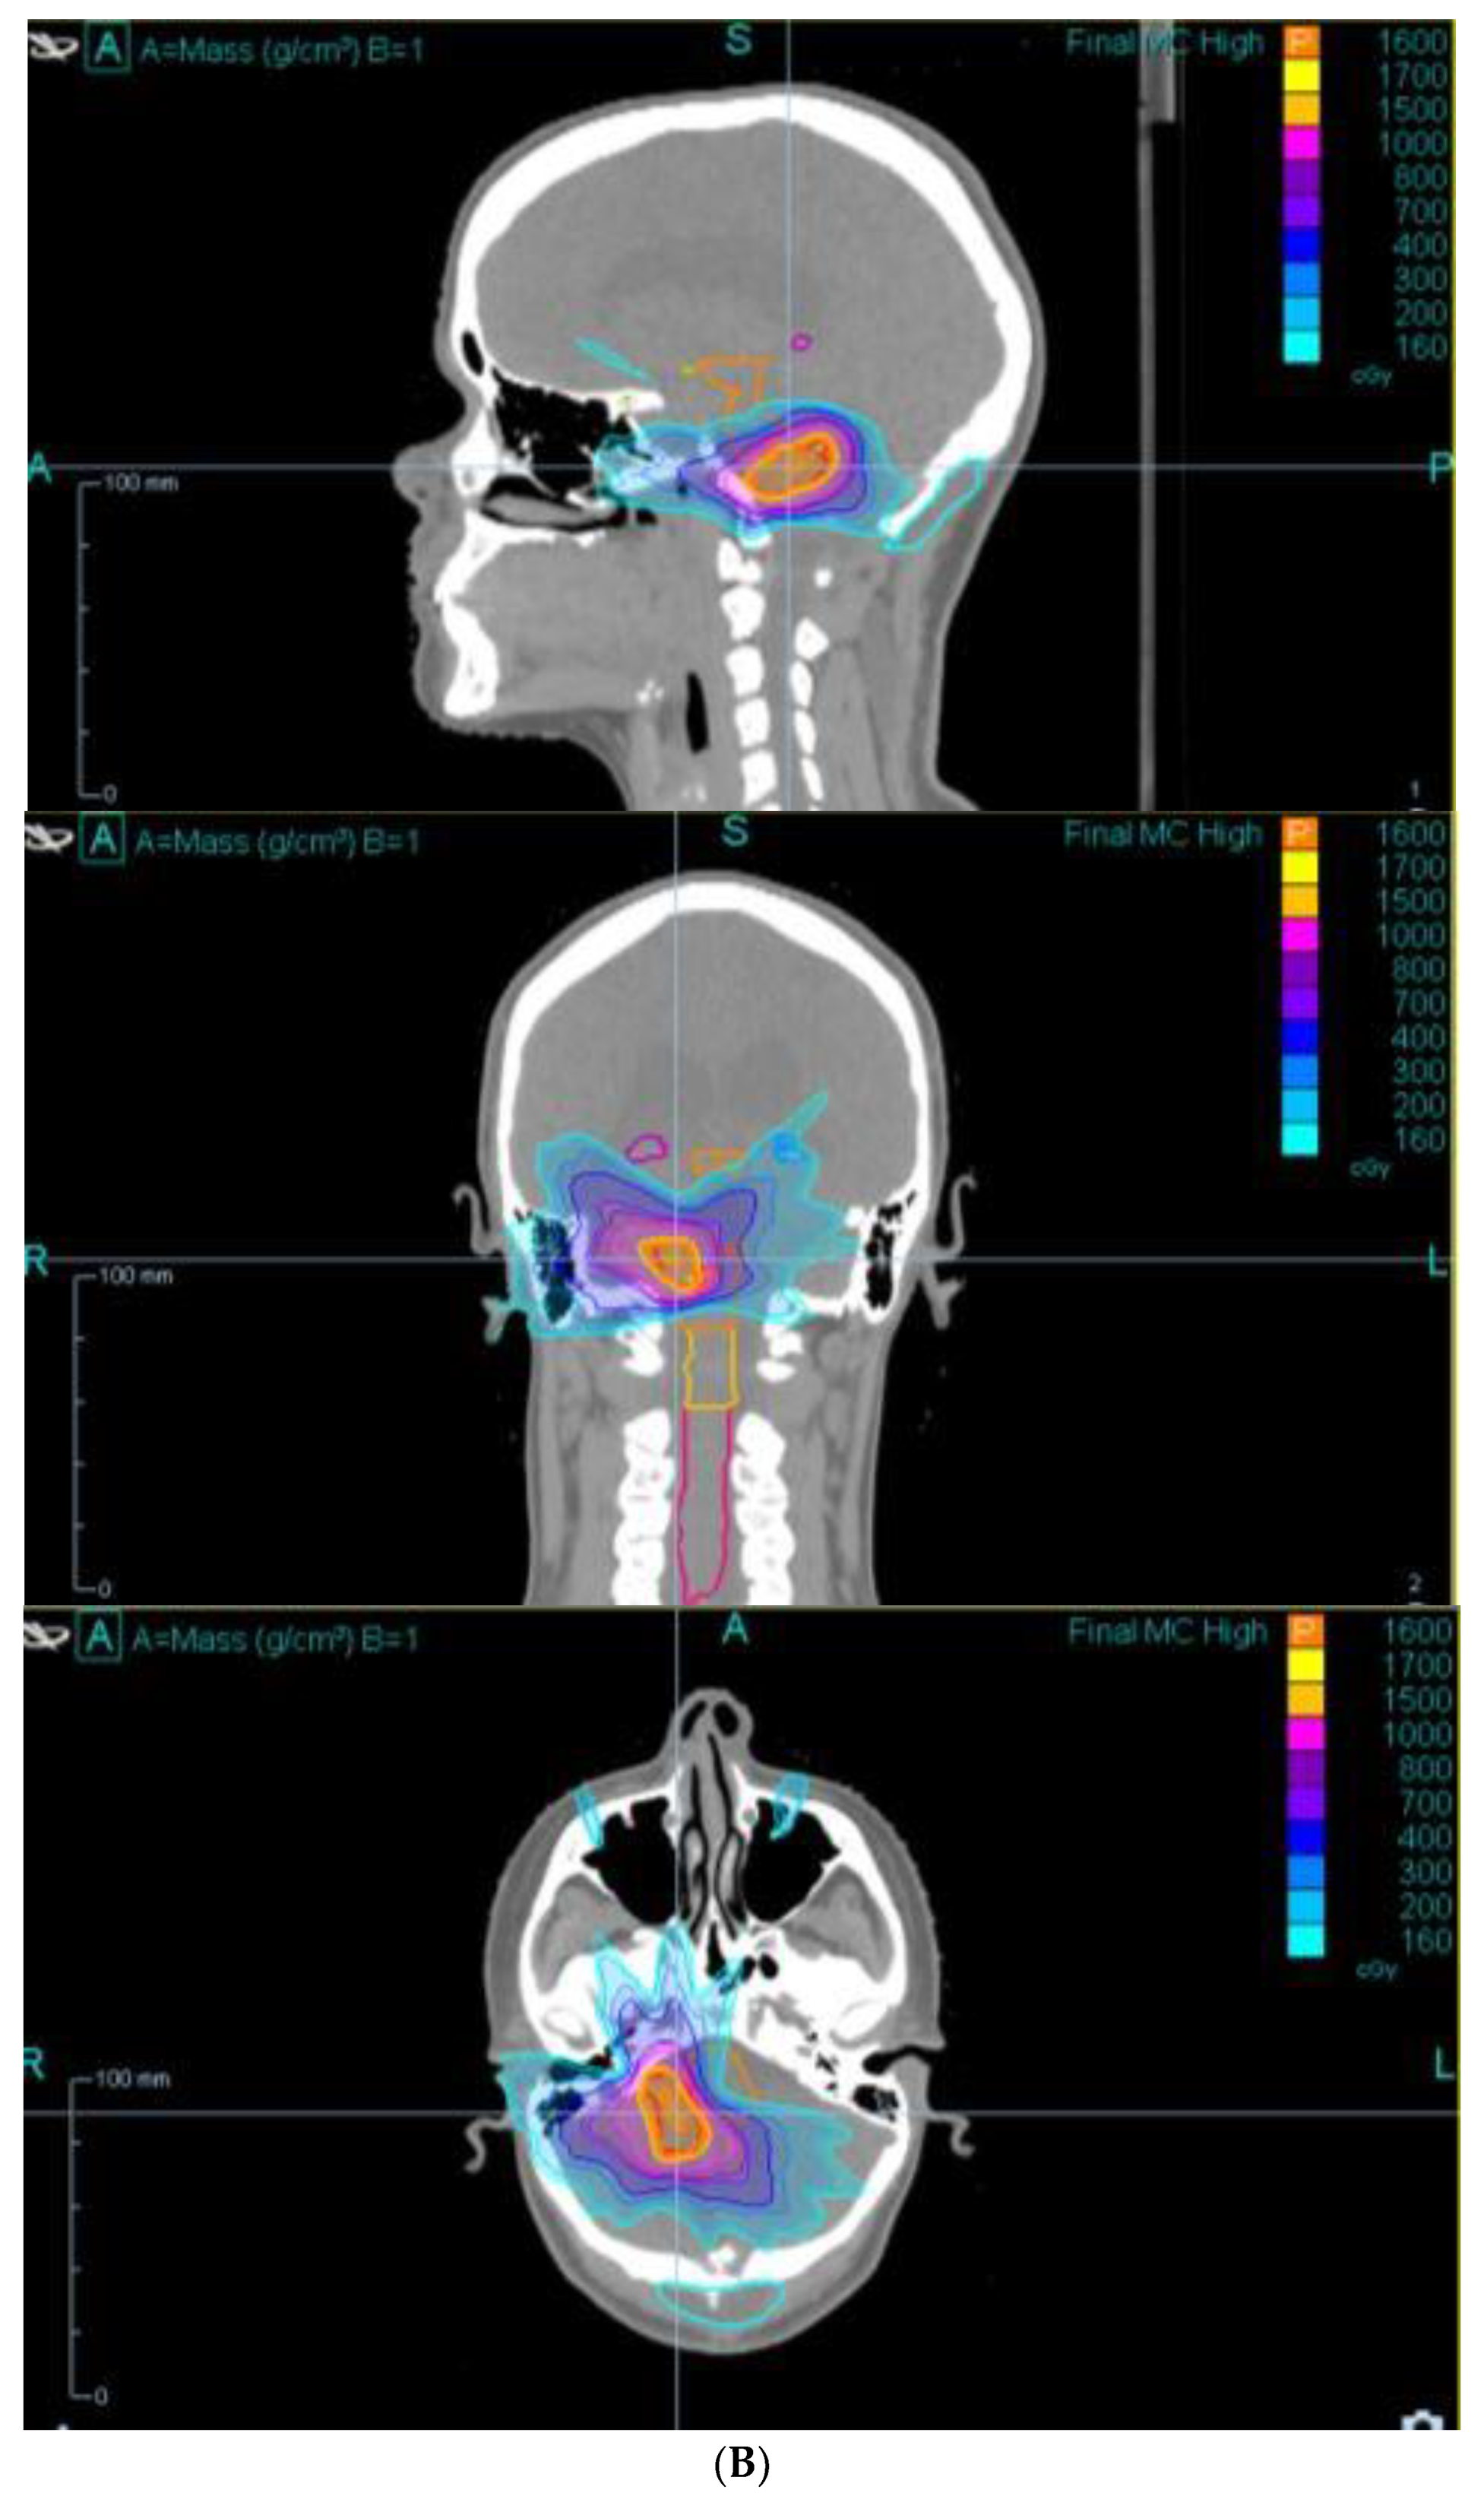

| Mejías et al./2022 [17] | To report CyberKnife treatment of large brain metastases from Ewing’s sarcoma. | 9-year-old boy treated with CyberKnife in two stages for brain metastases. | Complete resolution of lesions and good cognitive outcomes after 20 months. | Supports CyberKnife for large metastatic lesions in pediatric patients. |

| Mohamad et al./2020 [19] | To compare fractionated CyberKnife with IMRT in pediatric brain tumors. | 52 pediatric cases treated with CyberKnife. Dosimetry compared with IMRT. | CyberKnife reduced normal tissue radiation volumes without compromising local control (3-year local tumor control: 92%). | Fractionated CyberKnife reduces irradiated tissue volume; results warrant prospective validation. |